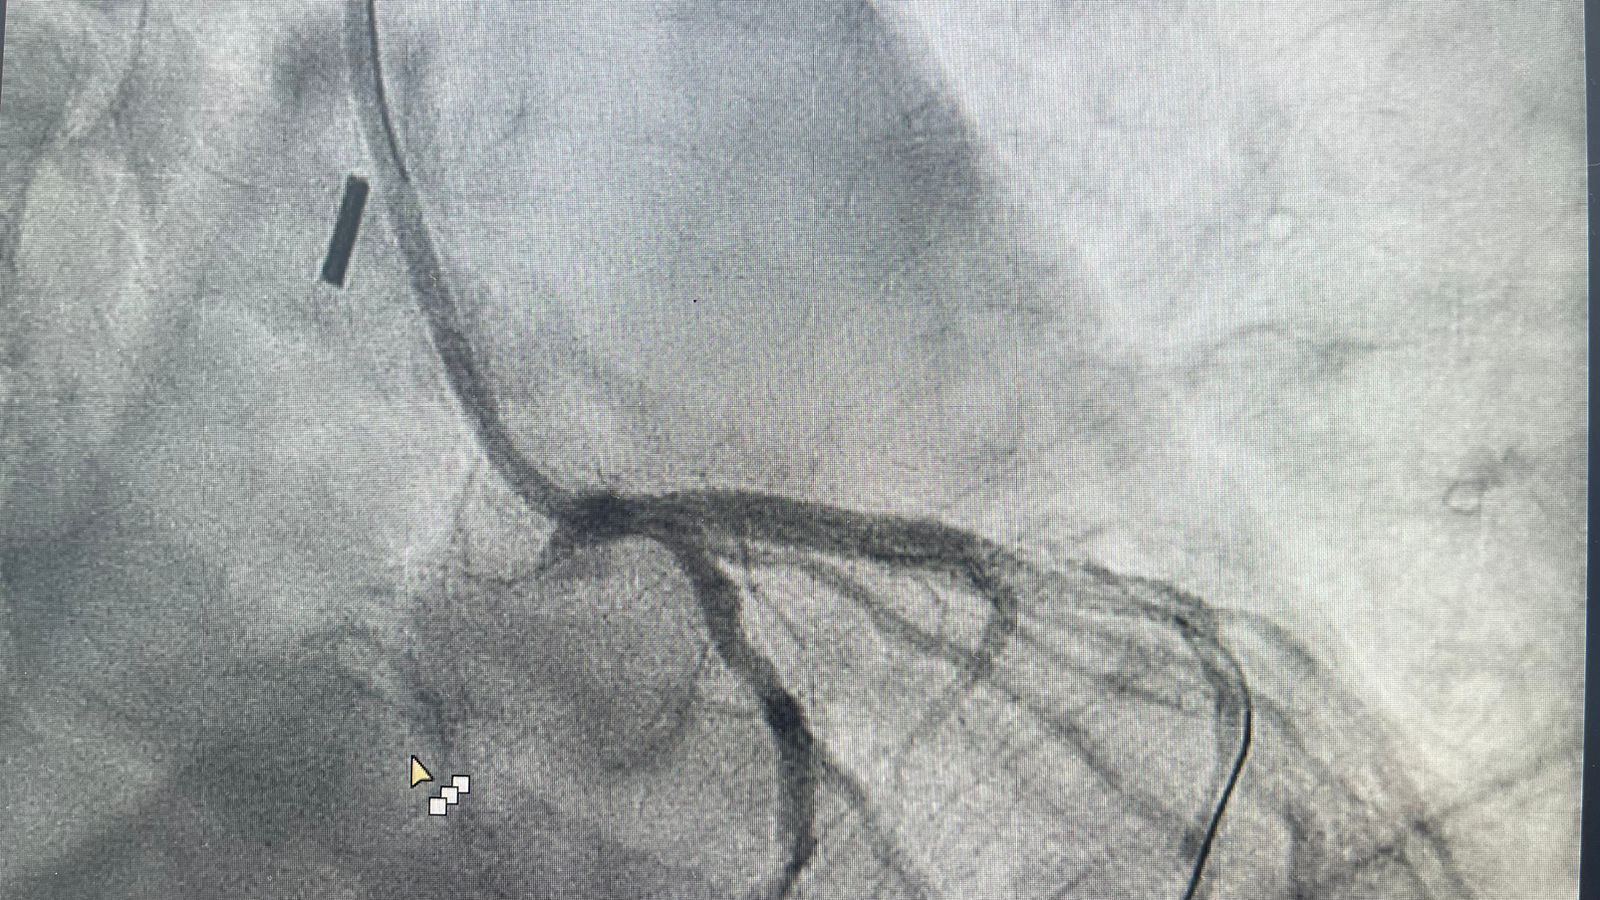

وقال الفريق الطبي المعالج بأنه بعد تفعيل مسار الجلطات القلبية ووصول الفريق الطبي من قسم القسطرة القلبية تم التعامل مع المريض وتبين أن هناك تضيق شديد بنسبة ٩٩ ٪ في الشريان الأيسر الرئيسي كاد أن يودي بحياة المريض ، حيث ان هذا الشريان يغذي ٧٠٪ من عضلة القلب ويحتاج الى تدخل جراحي عاجل لزراعة الشرايين “عملية قلب مفتوح”.

وأشار الفريق الطبي بأنه تم خلال القسطرة وضع مضخة داعمة للدورة الدموية في الشريان الأبهري لتحسين كفاءة عضلة القلب ووضع دعامة لفتح الشريان وتحسين تدفق الدم للعضلة واستقرار حالة المريض وتكللت ولله الحمد بالنجاح وتم متابعة حالة المريض وقد خرج في اليوم التالي.